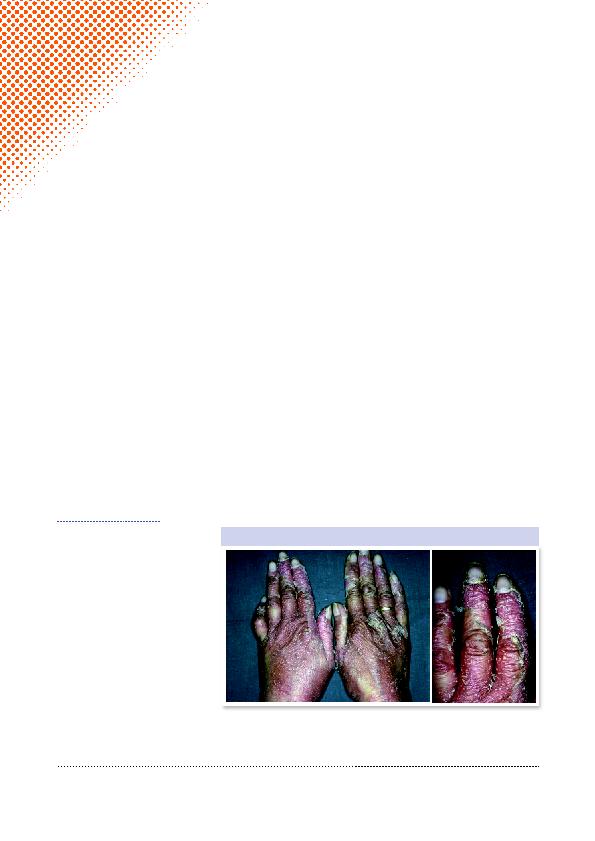

Figures 1 et 2: Psoriasis: pustules des mains avec érythème et desquamation dans un contexte

de psoriasis étendu.

Face à une pustulose palmo-plantaire,

différents éléments peuvent orienter le

diagnostic vers un psoriasis: la présence

d'antécédents familiaux ou personnels

de psoriasis, ou l'association à d'autres

lésions psoriasiques cutanées, un-

guéales ou muqueuses. Cliniquement,

il s'agit de pustules saillantes isolées

ou confluant en nappes, évoluant vers

des lésions sèches brunâtres ou des pla-

cards érythémato-squameux (Figures

1-3

). Le patient se plaint de prurit, de

douleur ou de brûlure et décrit souvent

un handicap fonctionnel important. Les

localisations préférentielles sont les

éminences thénar ou hypothénar aux

paumes (Figure 4) et la partie médiane

ou interne de la plante ainsi que les

talons. Contrairement à la dyshidrose,

l'éruption apparaît bien limitée et une

extension à l'entièreté de la paume ou

la plante est possible (Tableau 1).